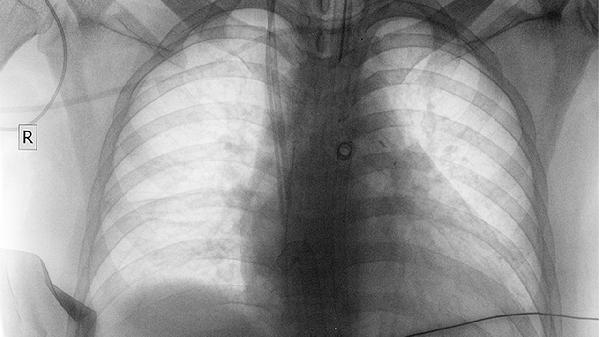

春季呼吸道疾病高发,但大多数肺炎症状轻微,只要没有上述危险信号,好好休息、对症处理,一般都能顺利康复。如果实在不放心,去医院做个血常规或胸片,也比自己瞎猜强!